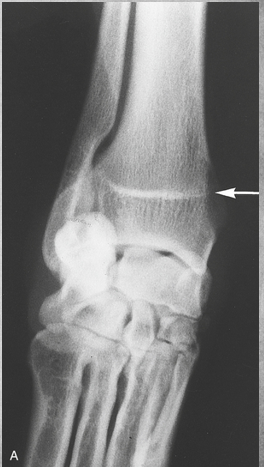

What does this depict?

Premature closure of growth plate distal radius.